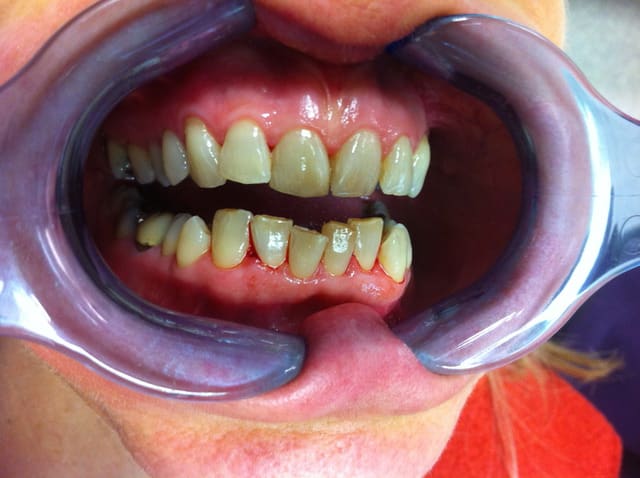

un cas qui me tient à coeur . j'ai pu sauvé toutes les dents après reprise des traitements canalaires et ma prothésiste a pas mal bossé

Agrys avant qpj067 - Eugenol

Photo 019 cr dy4tzg - Eugenol

Photo 446 cr cdjv8w - Eugenol

Photo 447 cr anuc1u - Eugenol

Photo 445 cr xbqinx - Eugenol